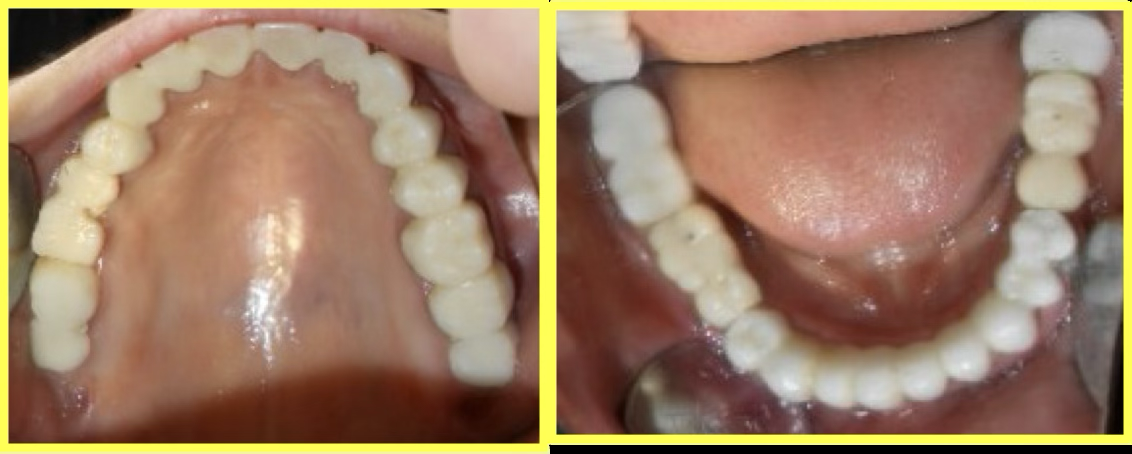

Final result

Permanent Porcelain Fused to Metal (PFM) crowns were custom-fabricated and cemented. Implants were delayed loaded after 3 months of healing.